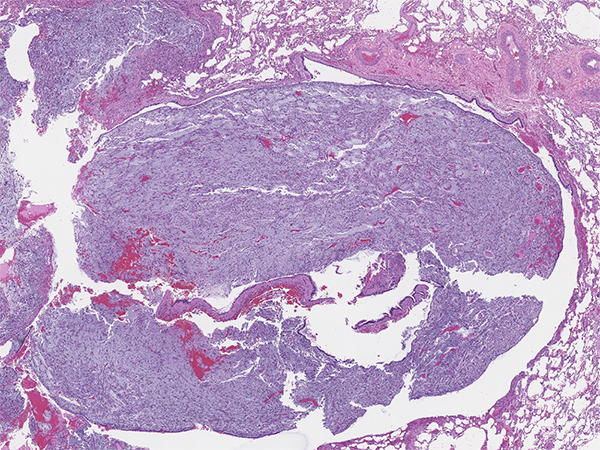

Inflammatory myofibroblastic tumor (IMT) is a mesenchymal neoplasm of intermediate biological potential composed of myofibroblastic cells associated with variable inflammatory infiltrate of plasma cells, lymphocytes and eosinophils. This tumor was given numerous names in the past, notably plasma cell granuloma and inflammatory pseudotumor. IMT can occur at any anatomic site, and comprises less than 1% of all lung tumors. It usually presents as a peripheral lung lesion, but in about 10-20% of cases can be endobronchial. Approximately half of patients with IMT are symptomatic. Local symptoms may be secondary to local growth and obstruction of the airways. Systemic symptoms are variable and include fever, night sweats, weight loss, accompanied by laboratory findings of anemia, elevated erythrocyte sedimentation rate and thrombocytosis. IMT has potential for local recurrence and rarely metastases.

IMT is a morphologically heterogenous neoplasm (Figures 1-6). Common morphologic patterns have been reported, each eliciting a broad differential diagnosis such as; inflammatory-rich, storiform reminiscent of nodular fasciitis and sclerotic scar-like. Cellular morphology varies from spindle, stellate to large ganglion-like cells with prominent nucleoli. The immunoprofile is rather non-specific and includes variable expression of smooth muscle actin (Figure 7), muscle-specific actin and desmin. Cytokeratin expression can be detected in about 30% of cases. ALK gene rearrangement resulting in expression of a chimeric fusion protein is found in approximately 50% of cases, mostly in children and younger adults. Detection of either ALK gene rearrangement or ALK protein overexpression (Figure 8) is diagnostically helpful. In contrast, ALK-negative IMT can be diagnostically challenging and essentially represents a diagnosis of exclusion. The differential diagnosis in ALK-negative cases include a wide spectrum of reactive/inflammatory processes on one end such as sclerosing mediastinitis, IgG4-related disease, pulmonary hyalinizing granulomas, and on the other end of spectrum malignant processes such as MALT lymphomas and sarcomas.